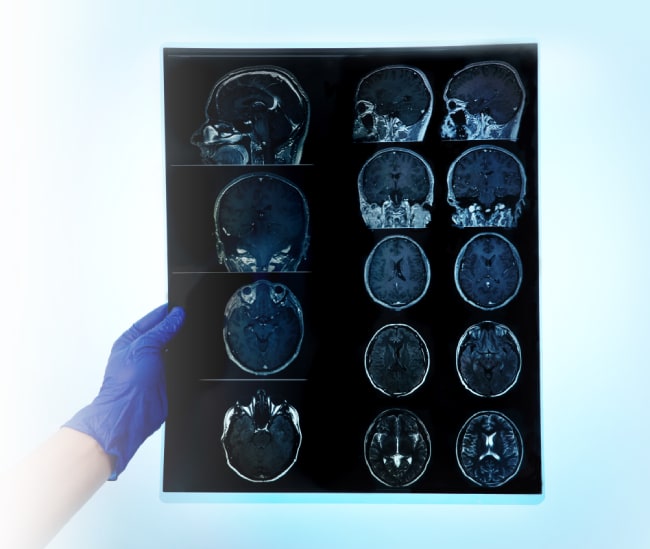

Для постановки диагноза проводится неврологический осмотр. Чтобы выявить изменения глазного дна, характерные для повышенного внутричерепного давления, назначается консультация офтальмолога.

Для визуализации патологии выполняются инструментальные исследования:

- МРТ головного мозга. Для оценки ликворотока может применяться фазоконтрастная ФК-МРТ.

- КТ головного мозга.

Обнаруженная коллоидная киста далеко не всегда требует немедленного лечения. Если образование некрупное и не проявляет себя клинически, врач может выбрать тактику наблюдения. Ежегодное проведение МРТ или КТ позволит оценить динамику процесса, склонность опухоли к росту.

Бессимптомная коллоидная киста может ничем не проявить себя на протяжении всей жизни пациента. Описаны случаи самопроизвольного уменьшения размеров образования. Тем не менее, такие случайные находки требуют регулярного наблюдения. Проходить МРТ или КТ-обследование нужно не реже раза в год. При малейших признаках неблагополучия — головных болях, головокружениях, тошноте, нарушении координации — необходимо немедленно обратиться за медицинской помощью.